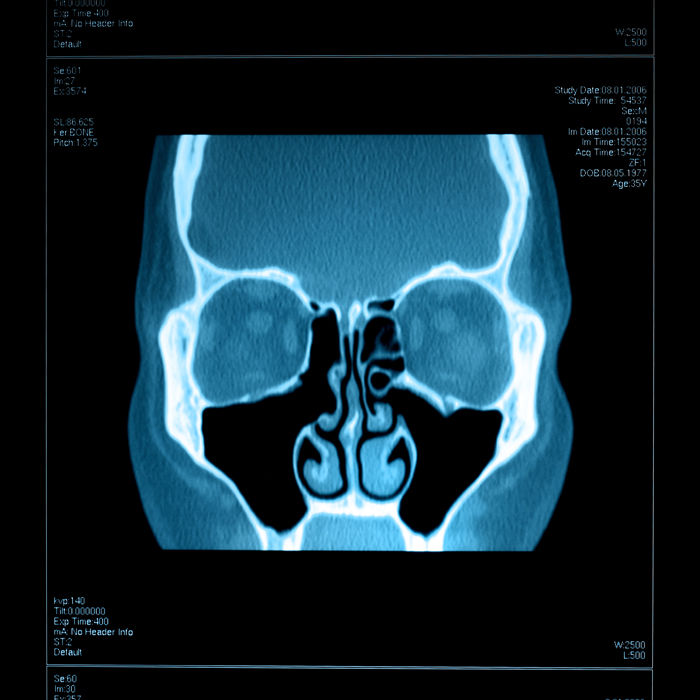

- Imaging: A CT scan of the sinuses can provide a detailed view of your sinus anatomy, revealing inflammation, infection, or structural issues.